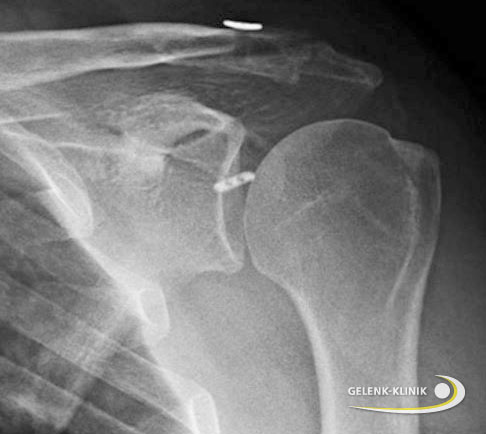

Früher wurden überwiegend Drahtcerclagen mit langen Drähten und einer Drahtcerclage durchgeführt. Diese sollen die Kräfte, die am hängenden Arm wirken, neutralisieren. Weiterhin sind sogenannte Rüsselplatten, also Platten, die auf dem Schlüsselbein verschraubt werden und unter dem Schulterdach Stabilisierung finden, vorhanden. Agmentationstechniken, also Fadenkordeln, welche die Bandstrukturen stabilisieren oder augmentieren, sind ebenfalls beschrieben worden. Ziel einer solchen Therapie ist es, eine Heilung ohne eine Verlängerung oder Elongation der Bandstrukturen zu ermöglichen.

Ein häufiges Problem bei diesen Behandlungsmethoden sind Verknöcherungen im Bereich der Bandstrukturen und meist auch eine Verlängerung in den Bändern. Um dies zu verhindern, wurden in den letzten Jahren zunehmend arthroskopische Verfahren zur Schultergelenksstabilisierung entwickelt. Einige Nachteile sind dadurch aufgehoben worden. Dieses zeitaufwendige und technisch anspruchsvolle Verfahren ist aus Sicht der Schulterspezialisten der Gelenk-Klinik die für den Patienten erfolgversprechendste und schonendste Methode.

Die Verwendung einer sogenannten Rüsselplatte ist ebenfalls ein Therapieverfahren, das bei Instabilität des Schultereckgelenkes eingesetzt werden kann.

Hier sind in den letzten Jahren vermehrt Anpassungen des sogenannten Rüssels der Platte, der unter dem Schulterdach zu liegen kommt, durchgeführt worden. Eine Verkürzung des Plattenkörpers lässt hier eine Verkürzung des Hautschnittes zu. Sie dient in erster Linie zur Versorgung bei frischen Verletzungen.

Die Indikation besteht ebenfalls bei AC-Gelenksluxationen Rockwood III-VI, lateralen Schlüsselbeinfrakturen sowie der Versorgung alter AC-Gelenkverletzungen in modifizierter Weaverdunn-Operationstechnik.

Die Platte ist anatomisch geformt und wird zum Teil auf dem äußeren Schlüsselbein mit 3-4 Schrauben befestigt. Der Halt wird am gegenüberliegenden Schulterdachknochen durch den sogenannten Rüssel gegeben.